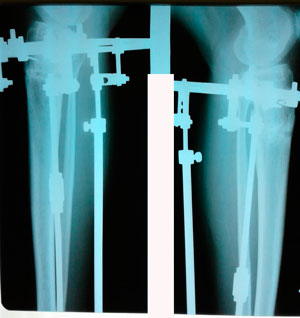

на фиксации

Вложения

IMG_8989-21-02-20-08-04.JPG

IMG_8988-21-02-20-08-04.JPG